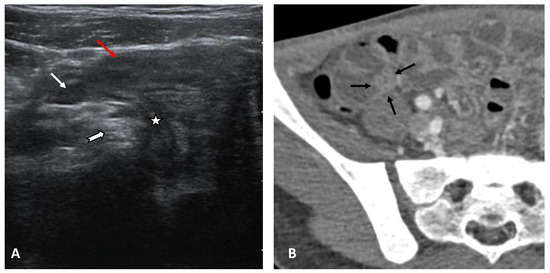

- Abnormalities of the hollow visceral organs, including distension and wall thickening of the gallbladder (Figure 4), stomach, bowel, small bowel (Figure 5A, and urinary bladder (on CT and ultrasound). They were considered thickened if >3 mm. Additionally, the cross-sectional diameter of appendix is considered enlarged if >6 mm (Figure 5B).

- Mesenteric and retroperitoneal lymphadenopathy (Figure 7) with mesenteric lymph nodes considered enlarged if >5 mm in short axis and retroperitoneal lymph nodes considered enlarged if >9 mm in short axis.